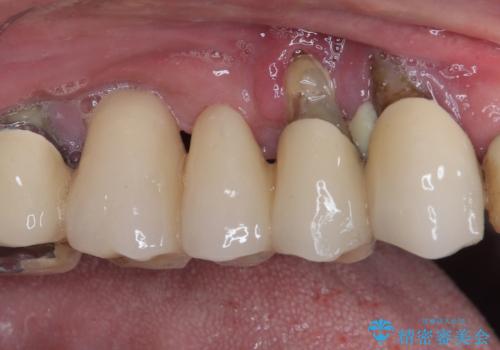

- 奥歯がぐらぐらして噛めないとのことで来院された患者様です。

ブリッジの土台となっている歯は全て抜歯が必要な状態であったため、事前に仮歯を用意して、極力抜歯と同時にインプラントを埋入し、速やかに仮歯を装着して噛めるように処置を進めて行くこととしました。

手前の歯は骨の欠損が著しいため、抜歯後暫く待ってから埋入を行うこととしました。